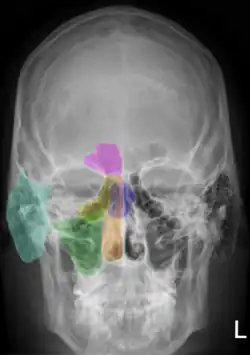

Рентгеноанатомия

Рентгеноанатомия (рентгеновская анатомия) — теоретическая дисциплина на стыке анатомии и рентгенологии, изучающая структурные закономерности рентгенографических изображений тела человека. Индивидуальные и возрастные рентгеноанатомические варианты строения рассматривает клиническая рентгеноанатомия. Функциональные особенности анатомических структур изучаются функциональной рентгеноанатомией.

Выделение рентгеноанатомии, как самостоятельной анатомической дисциплины, обусловлено характером получения изображения внутренних структур организма при рентгенографии. Рентгеновский снимок представляет собой двухмерное изображение трёхмерного объекта, что сопряжено с проекционным наслоением различных анатомических структур; это требует наличия определённых навыков для корректной трактовки подобных изображений. С учётом возможностей рентгенографии, выделяют рентгеноанатомию костей скелета, органов грудной клетки, других внутренних органов (пищеварительной, сердечно-сосудистой, мочеполовой систем и др.).

Рентгеноанатомия костей.

Присутствие солей кальция в костях делает их менее «прозрачными» для лучей рентгена, чем окружающие мягкие ткани; при этом в связи с различиями в гистологической структуре компактного и губчатого вещества кости отличается и характер их рентгеновского отображения. Компактное вещество кости образует на рентгенограмме интенсивную «тень» в виде светлых полос большей или меньшей ширины, а губчатое — ячеистый, сетеподобный рисунок.

В местах соединения костей друг с другом отмечается тёмная полоса («полоса просветления») — рентгеновская суставная щель, отграниченная более светлыми линиями субхондральных отделов сочленяющихся костей. Ширина рентгеновской суставной щели зависит от толщины «прозрачного» для рентгеновских лучей суставного хряща.